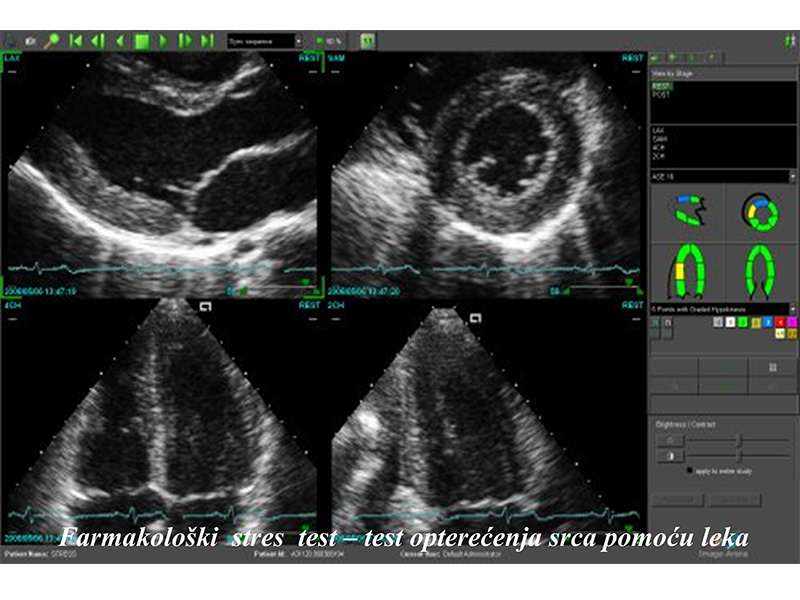

* Heart stress testing: ergometry, pharmacological stress test – STRESS ECHO

Ergometry – test in which the heart is stressed through a physical activity such as riding a bicycle, while performing an ECG and monitoring the artery pressure. It’s applied for chest pains, angina pectoris possibility and estimation of severity, after myocardic arrest and for high artery blood pressure or disorders in heart rate.